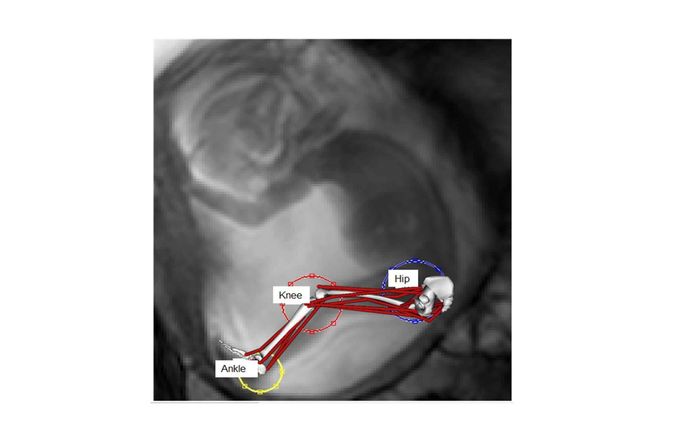

London Lower Limb model

Musculoskeletal modelling

Knowledge of the internal loads acting on the human body during daily life movements has a wide range of applications, from clinical assessment of motor control patterns to prosthesis design and preclinical testing and as an input for finite element models predicting bone adaptation.